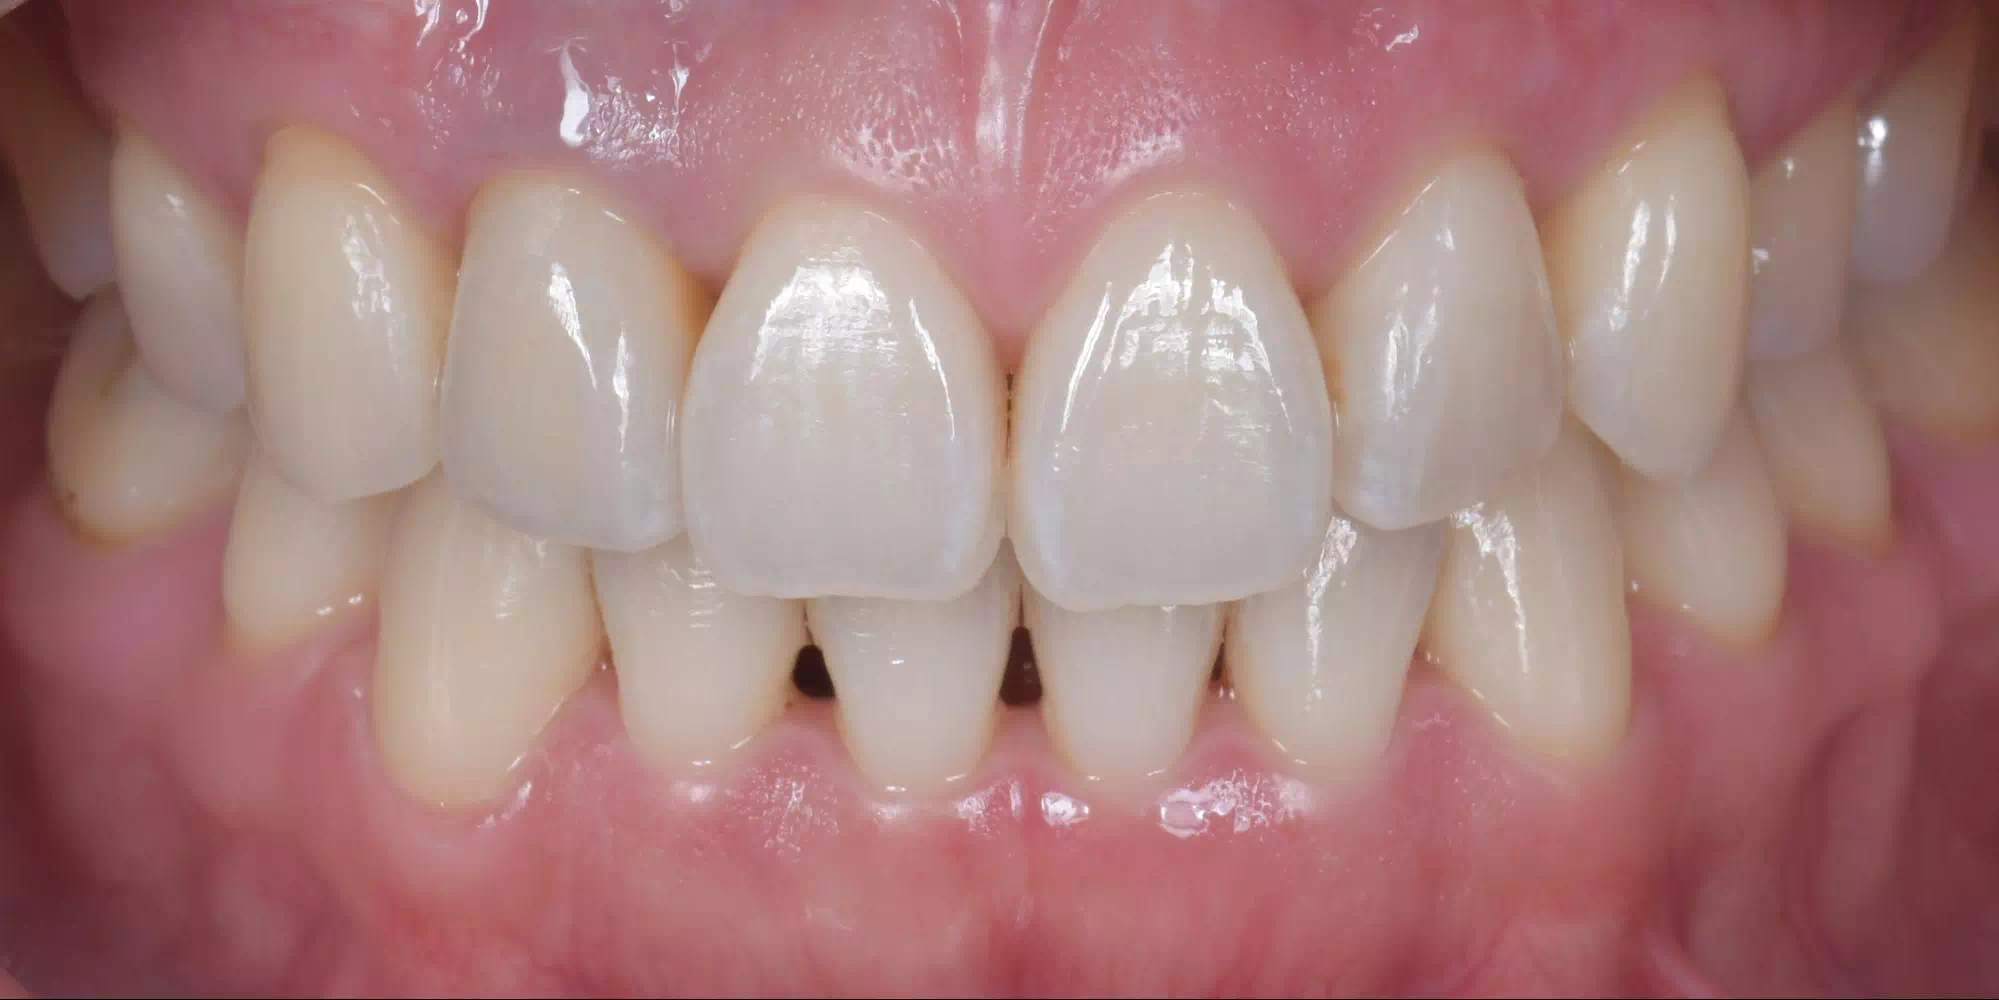

CASE HOME CASE 2025/10/21 抜歯即時埋入・即時荷重 症例 2025/10/21 GBR① 2025/10/21 インプラント 症例② 2025/10/21 インプラント 症例① 2025/10/21 矯正歯科 症例 2025/10/21 審美歯科 症例② 2025/10/21 審美歯科 症例① 2025/10/21 ガミースマイル 症例 2025/10/21 歯肉再生 症例② 2025/10/21 歯肉再生 症例① 2025/10/21 虫歯症例